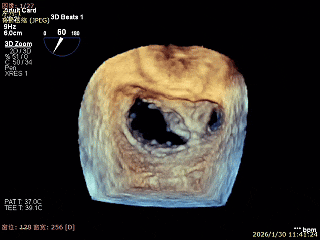

3D Enface 2区及3区前叶脱向左房

3D Enface 可见反流由2区3区从前后冲出

3D Enface下组织桥稳定残余外侧前叶脱垂

3D Enface上彩可见夹子内侧无反流,残余外侧反流

3D Enface下组织桥稳定无反流

夹子释放后,反流基本消失

LVOT切面可见主瓣二尖瓣术后反流基本消失